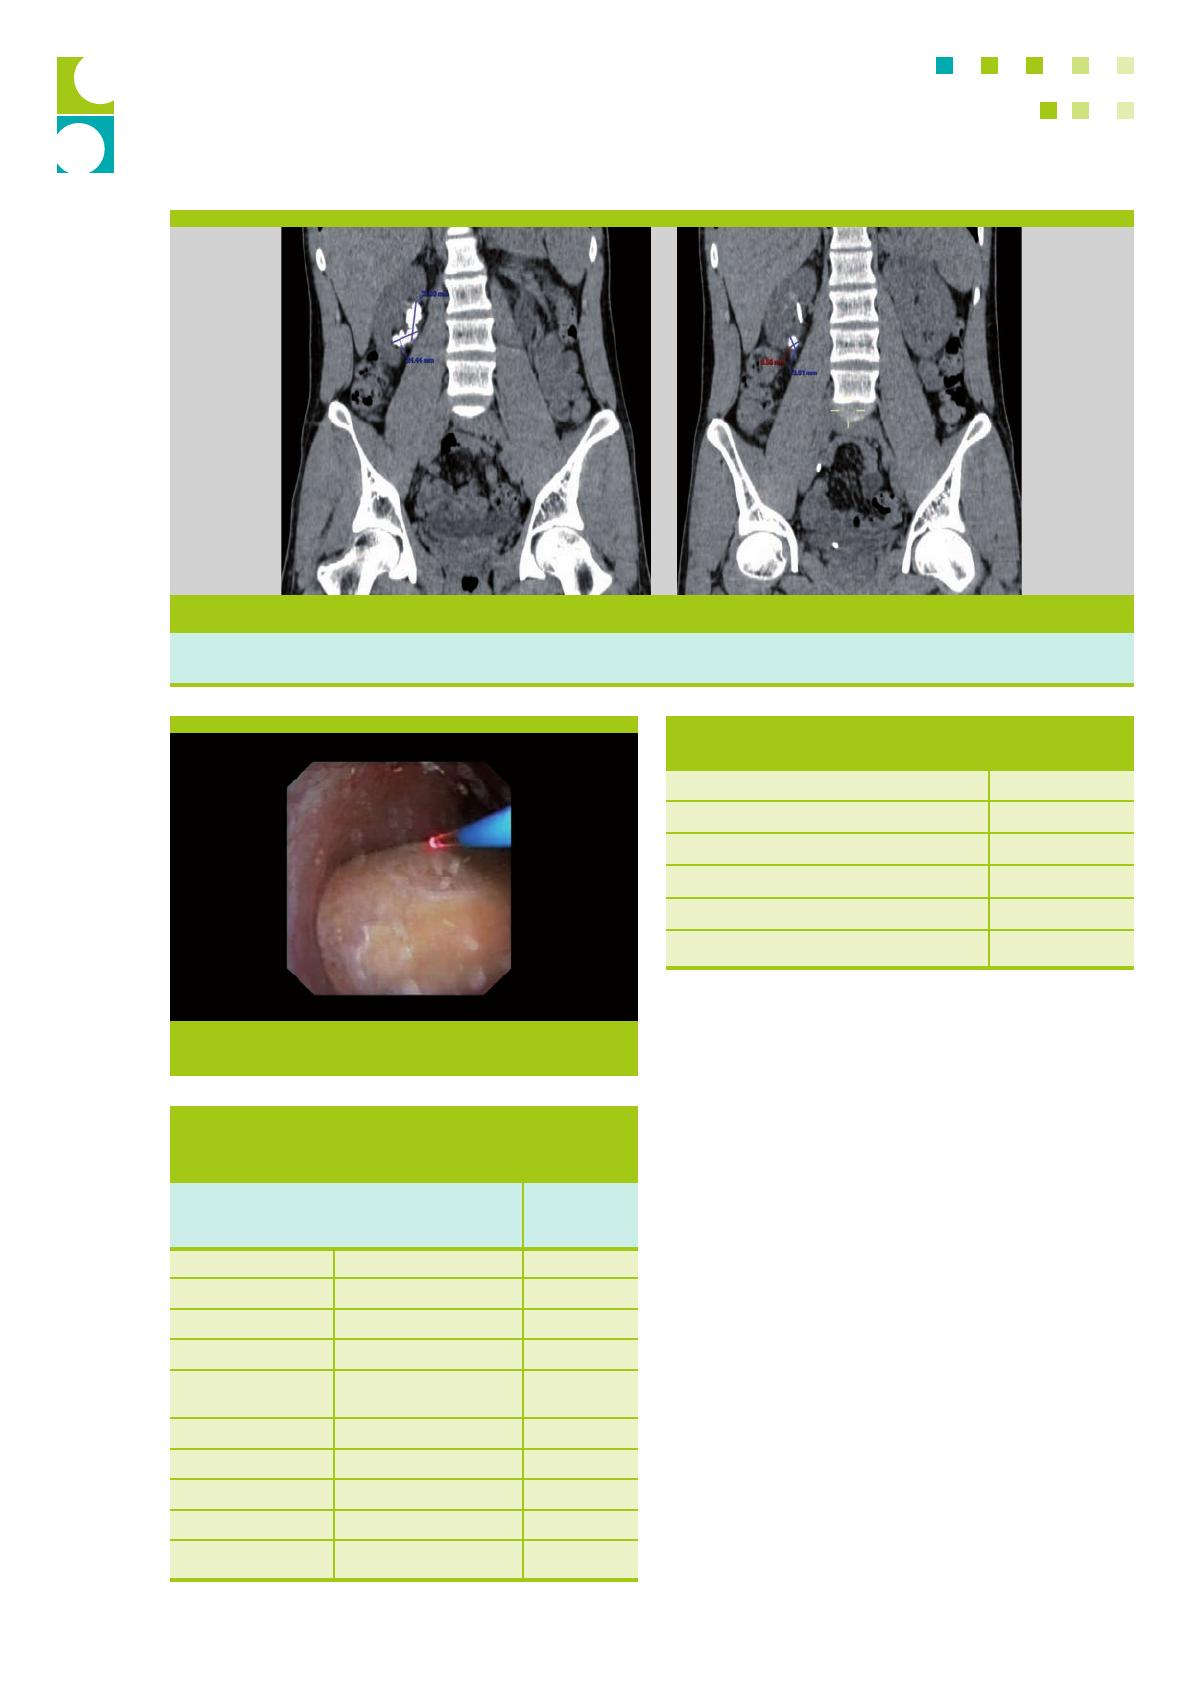

Néphrolitholapaxie percutanée

La néphrolitholapaxie percutanée (NLPC) est la techni-

que de choix pour les calculs de grande taille (L 20 mm)

situés dans le système pyélo-caliciel.6 D’un point de vue

technique, la mise en place d’une sonde urétérale par voie

rétrograde permet de dilater le système pyélo-caliciel, ce

qui facilite l’accès percutané du rein sous contrôle échogra-

phique et/ou fluoroscopique. Le site de ponction est choisi

non seulement en fonction de la localisation et du volume

du calcul, mais aussi de la situation anatomique. Différents

générateurs d’ondes de fragmentation sont utilisés : les gé-

nérateurs à ultrasons, le lithotripteur pneumatique (litho-

clast) ou le laser Holmium-YAG. Le choix du système dépend

de la charge lithiasique et du diamètre du néphroscope.

La NLPC classique nécessite une dilatation du trajet per-

cutané jusqu’à Charrière 30 (= 1 cm). La fragmentation et

l’extraction des calculs de gros volume en sont grandement

facilitées (figure 1).